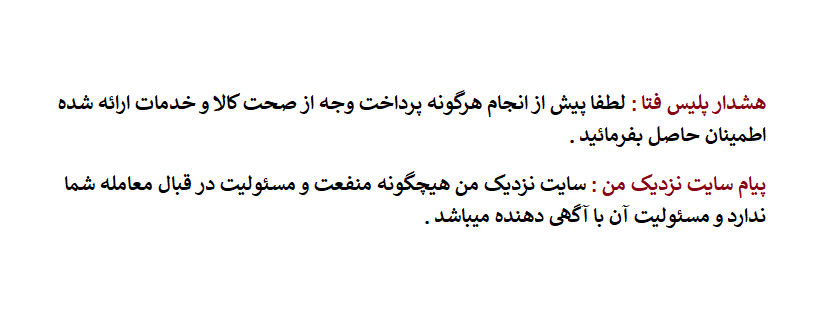

-ساخت تعمیر دندان مصنوعی

-چسباندن و ترمیم شکستگی

-روکش پی اف ام و زیرکنیا

-قالبگیری ساخت تعمیر ترمیم انواع دندان مصنوعی

در این هنگام معمولا دندانپزشکان از دهان بیماران قالبهایی میگیرند که نیاز است برای آنها ایمپلنت، بریج و روکش ساخته شود. ساخت این موارد بر عهده دندانساز است.